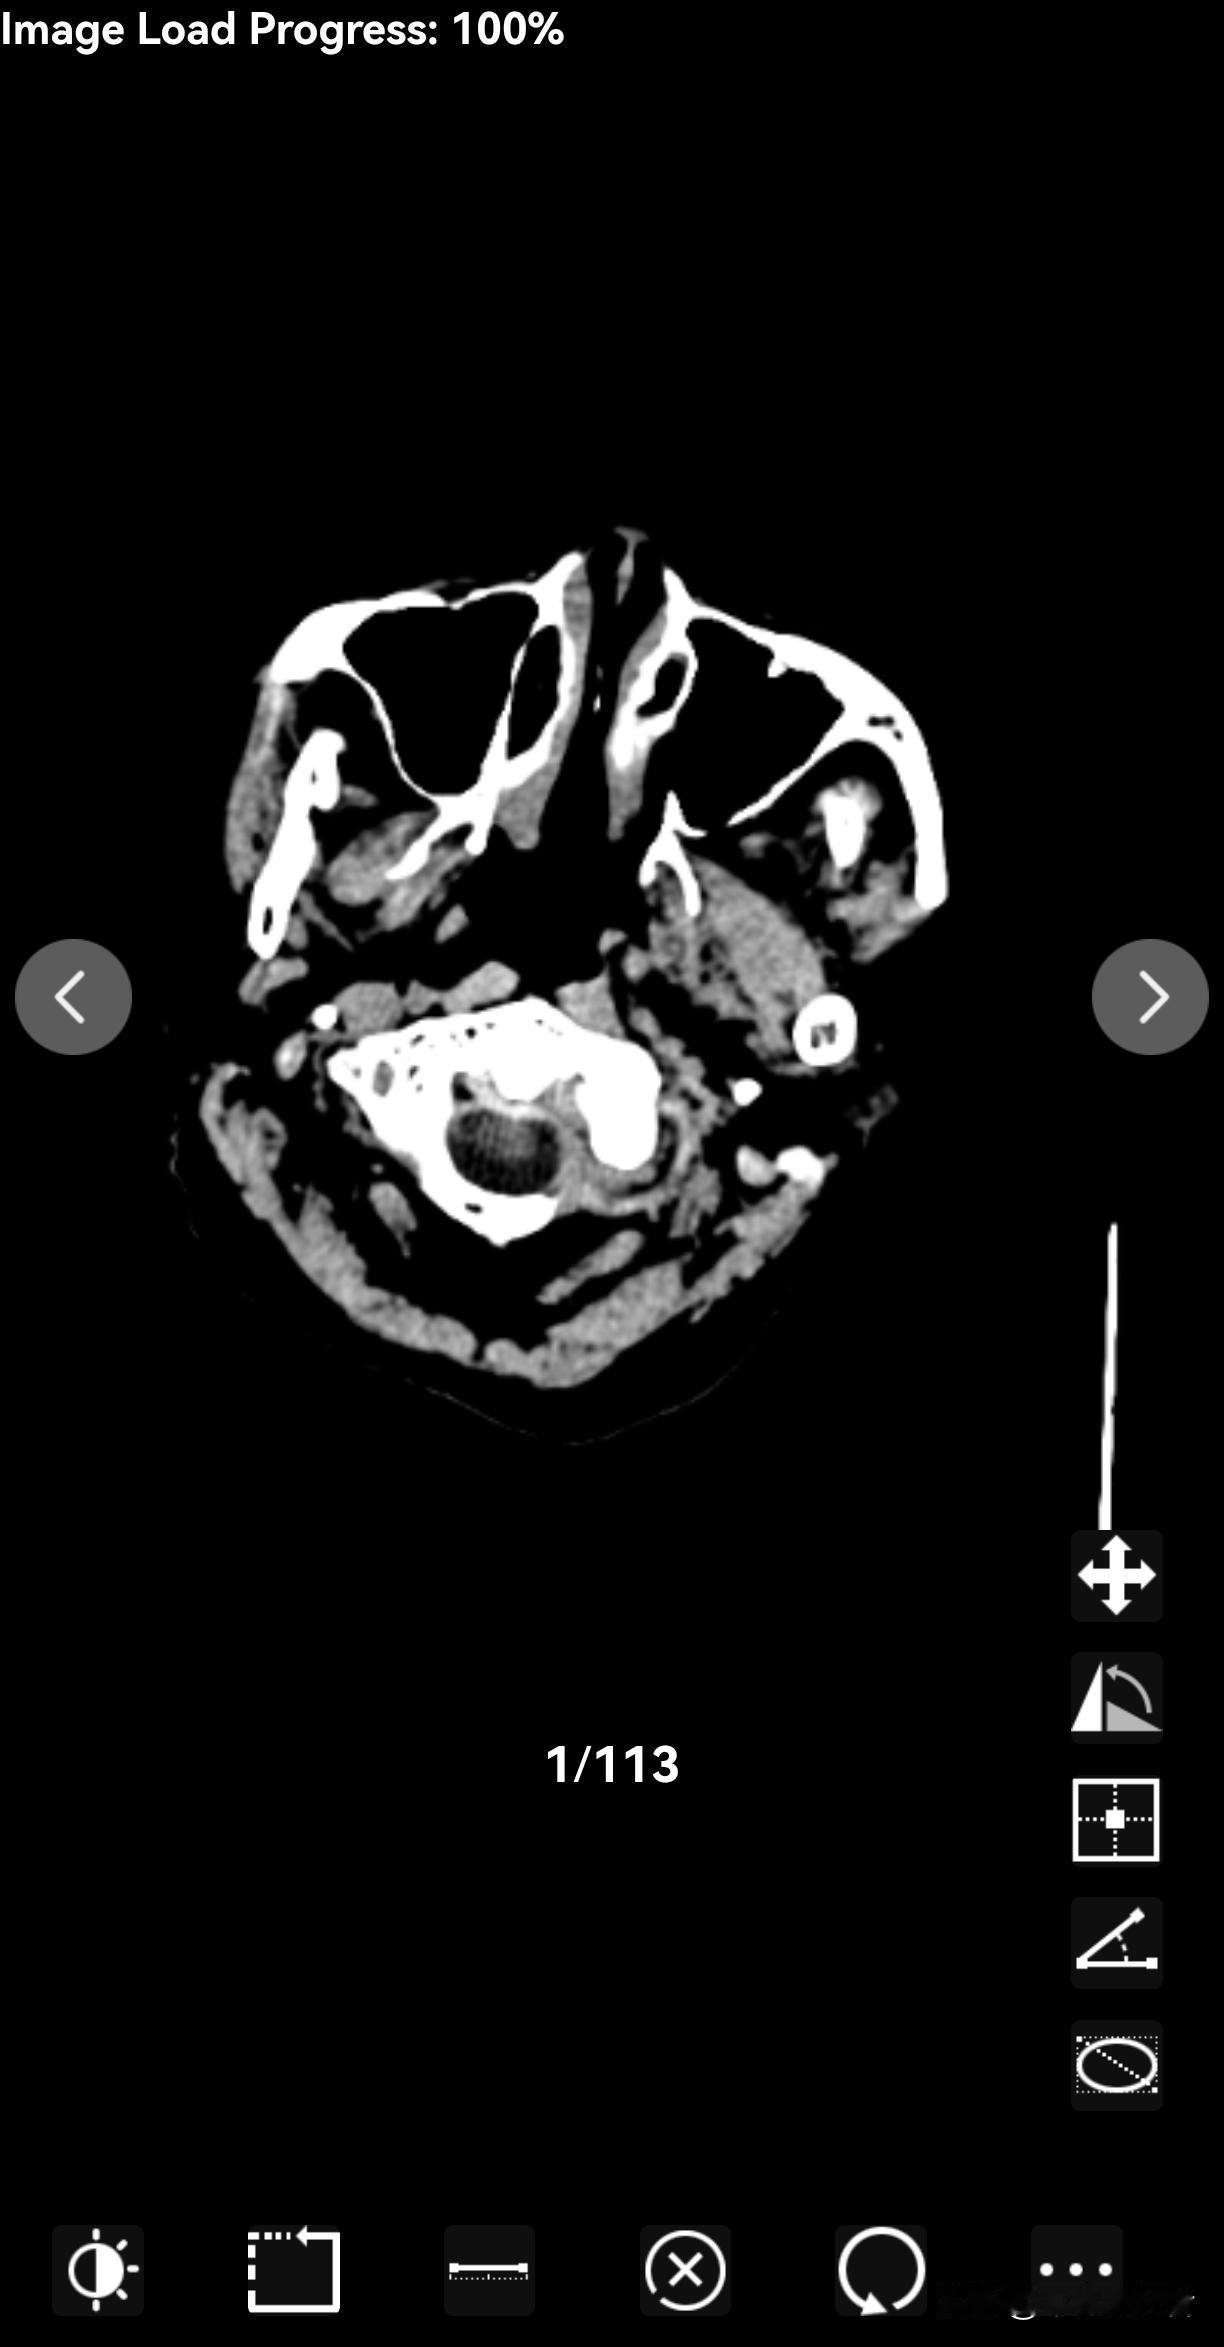

我的一个朋友,2016年的时候检查出肌酐400多,医生就叫他做瘘。他当时坚决不同意,医生说不做的话后果自负,可他还是坚持先住院调理。出院后主任开了十种药,每两个月一疗程,就这么硬扛了快十年。今年一月份,肌酐飙到800多,贫血、吃不下饭、总吐,实在扛不住才做了瘘透。 说实在的,我挺佩服他的毅力——十年坚持吃药控制指标,换谁都不容易。但咱也得明白,肌酐400多真不是小事儿。正常肌酐100以下,400多说明肾功能只剩10%-20%,离尿毒症不远了。医生让做瘘,是因为肌酐高到一定程度(像707以上)就得透析,而瘘是透析的“生命通道”,提前做好能让后续治疗更顺。 朋友总说“能吃药尽量吃药”,这心态咱能理解——谁都怕动刀子。但现在看,拖了十年才做瘘,虽然多扛了段时间,可最后还是得面对。其实医生建议提前造瘘,也是为了给治疗留余地。要是遇到类似情况,多和医生聊聊,把手术风险、药物控制的极限都弄清楚,再做决定可能更踏实。毕竟,治病没有“一刀切”的选择,咱得把账算明白。